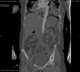

Leriche syndrome

In medicine, aortoiliac occlusive disease, is a form of central artery disease involving the blockage of the abdominal aorta as it transitions into the common iliac arteries. Signs and symptoms Classically, it is described in male patients as a triad of the following signs and symptoms: claudication of the buttocks and thighs absent or decreased femoral pulses erectile dysfunctionThis combination is known as Leriche syndrome. [Source: Wikipedia ]